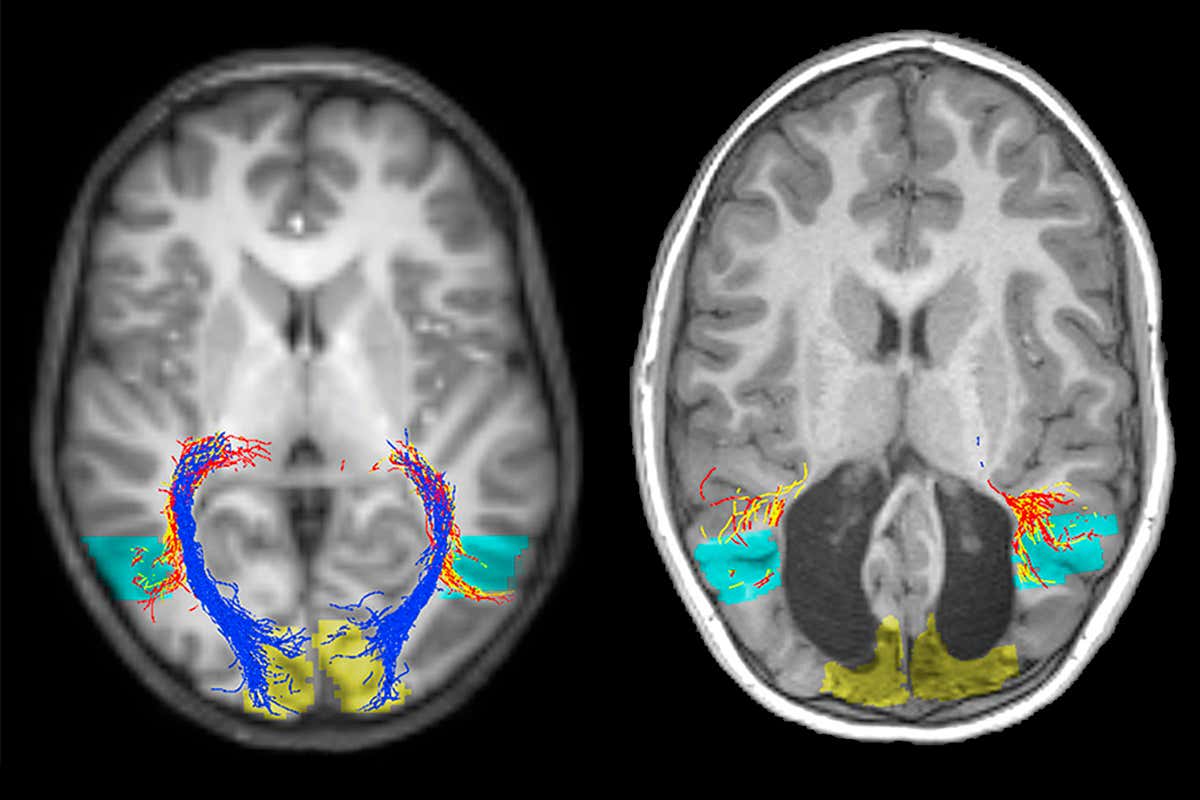

A normal brain (left) and the boy missing a visual cortex (right) Description:Inaki-Carril Mundinano,Juan Chen,Mitchell de Souza,Marc G. Sarossy,Marc F. Joanisse,Melvyn A. Goodale,James A. Bourne

An Australian boy missing the visual processing centre of his brain has baffled doctors by seeming to have near-normal sight.

The 7-year-old, known as “BI”, lost his primary visual cortex shortly after he was born due to a rare metabolic disorder called medium-chain acyl-Co-A dehydrogenase deficiency.